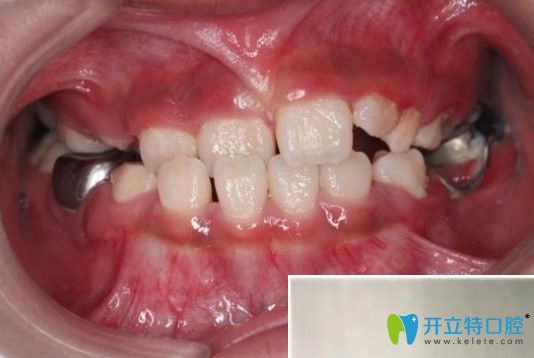

醫(yī)生給孩子檢查口腔時(shí)候拍的照片,特別認(rèn)真,動(dòng)作很輕柔▼

杭州兔牙醫(yī)醫(yī)生給孩子檢查口腔時(shí)候拍的照片

這是我家女兒的牙齒照,以前沒(méi)關(guān)注過(guò)▼

孩子地包天在凸牙醫(yī)做矯正前的牙齒圖